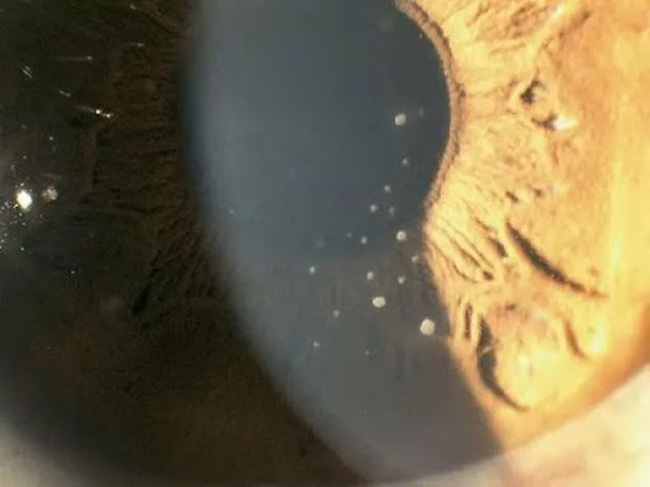

Bác sĩ kiểm tra cho Tiểu Khiết phát hiện IOP (áp lực nội nhãn) ở mắt phải của cô cao tới 55mmHg (IOP bình thường là 10-21mmhg), kết mạc của mắt phải xung huyết nhẹ, phù nề biểu mô giác mạc, và một số cặn lắng được nhìn thấy ở phía sau giác mạc, Tiểu Khiết được chẩn đoán là bệnh tăng nhãn áp.

Hình ảnh một số cặn lắng được nhìn thấy phía sau giác mạc